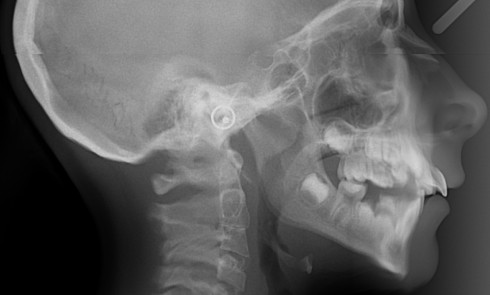

Article réservé à nos abonnés Gestion orthodontico-chirurgicale d’un cas de béance et importance de la prise en charge fonctionnelle

Les béances dentaires sont des malocclusions difficiles à traiter. Les troubles fonctionnels sont souvent à l’origine du problème, et leur...